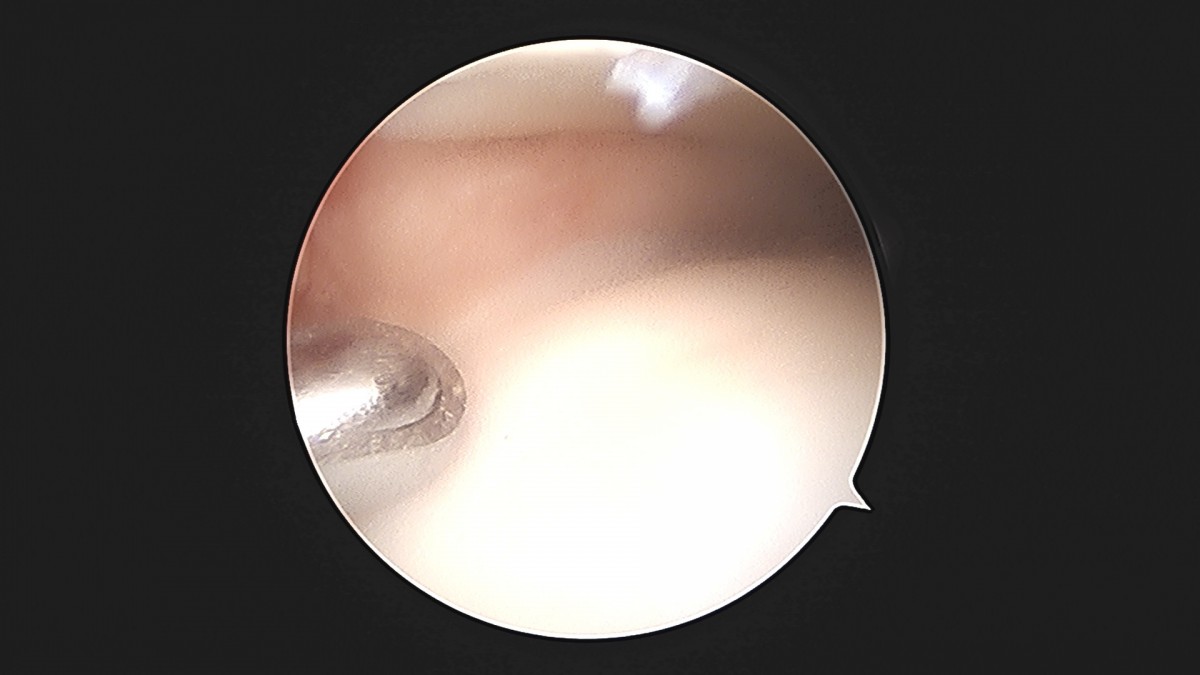

이재상원장님 발목 활액막 절제술 및 인대 봉합술 이승O 환자

작성자 최고관리자 댓글 0건 조회 787회 작성일 25-09-16 15:24